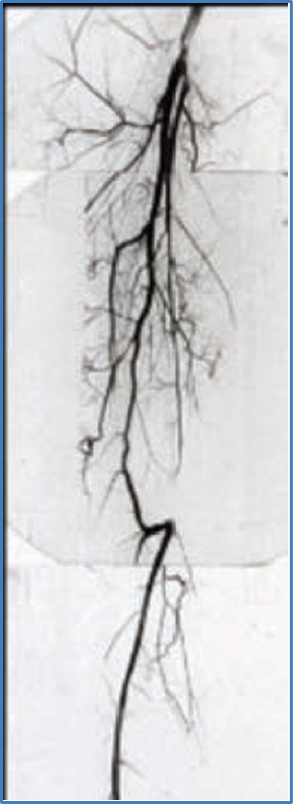

The Vascular International (VI) School for Vascular Surgery is dedicated to advancing the training and education of vascular surgical techniques through the use of lifelike models. With patient safety as the top priority, VI continuously strives to enhance vascular surgery training, ensuring the highest standards of safe and effective open and endovascular patient care.